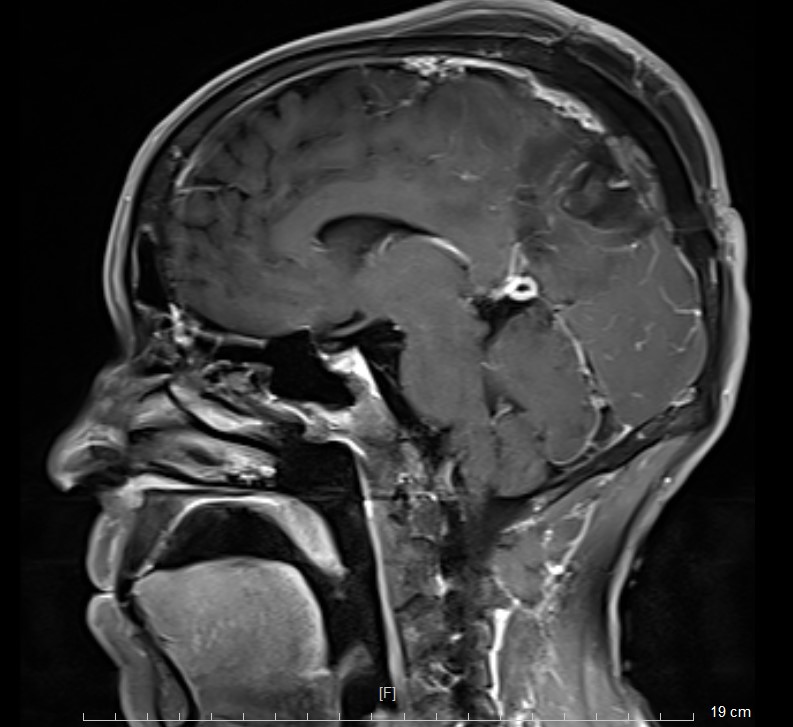

头部MR检查提示:左顶枕镰旁脑膜瘤

术后MR复查提示肿瘤切除干净